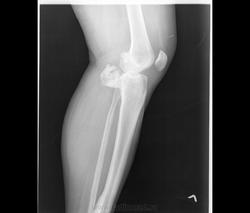

После рентгенографии и КТ направительный диагноз "костно-хрящевой экзостоз проксимального эпифиза, гиперостоз диафиза левой б/берцовой кости".

Коллеги, я же написала, что "остеохондрома (экзостоз)" был направительный диагноз, который сняли, проведя рентгеновское дообследование. Для экзостоза характерно: ножка исходит и имеет структуру губчатой кости, корковый слой переходит снаружи на ножку. Здесь образование исходит из коркового слоя (видно на КТ). Кроме того я указала, что в направительном диагноза (видно в нижних отделах бокового снимка) есть гиперостоз диафиза б/берцовой кости.

Обратите внимание, помимо гиперостоза, в дистальном эпифизе б/берцовой кости, 1 плюсневой кости и проксимальной фаланге 1 пальца - внутрикостные очаги склероза. Т.о.: гиперостоз, остеосклероз и гететопические оссификаты костей левой нижней конечности.

Микроскопическая картина: фрагменты костных балок с явлениями гиперостоза, утолщенные элементы ламеллярной кости на отдельных участках с резким сужением и облитерацией гаверсовых каналов, очаговый межбалочный фиброз с замещением элементов жирового костного мозга.